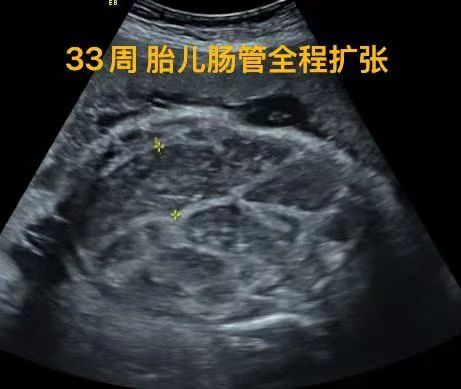

33周時,超聲復查發現寶寶開始出現明顯的腸管全程擴張,考慮腸梗阻/腸道閉鎖可能。